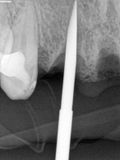

fredlibc | all galleries >> Galleries >> MTiu - immediate 12 and 21 > R1 (1).jpg

R1 (1).jpg